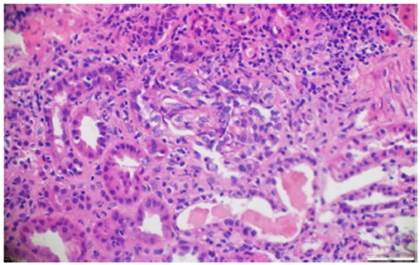

Paraclínicos de ingreso evidenciaron anemia (hemoglobina de 8,9 g/dL), hematuria y proteinuria (75 mg/dL) en muestra espontánea de orina, elevación de azoados (BUN = 45 mg/dL, creatinina sérica = 2,9 mg/dL), complemento sérico C3 y C4 normales, anticuerpos antinucleares y anticuerpos antimembrana basal glomerular negativos, PR3-ANCA negativo < 3,5 U/mL (negativo < 5 U/mL) y MPO-ANCA positivo 72 U/mL (negativo < 5 U/mL). Al ingreso se sospechó glomerulonefritis postestreptocócica complicada versus nefritis lúpica. Ante el aumento progresivo de los azoados y del deterioro clínico de la función renal, se requirió inicio de hemodiálisis y practicar biopsia renal.

La patología renal mostró proliferación crescéntica activa de origen celular, con actividad alta, necrosis fibrinoide extensa, infiltración leucocitaria y evidencia de infiltrado linfoplasmocitario en el intersticio, asociado a 10% con fibrosis. No había evidencia de depósitos de complejos inmunes (figs. 3 y 4).

Figura 3 Hematoxilina y eosina. Extensas semilunas celulares que colapsan el penacho glomerular. 10x.

Figura 4 Hematoxilina y eosina. Semilunas fibrocelulares con obliteración de la luz capilar en el penacho glomerular. 10x.